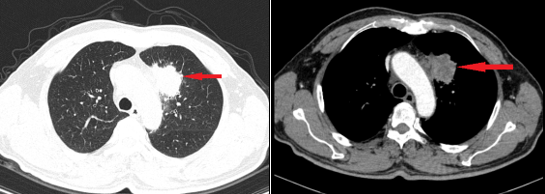

Qua thăm khám và chụp CT lồng ngực, bác sĩ phát hiện nam bệnh nhân có khối u ở thùy trên phổi trái, được xác định là ung thư biểu mô tuyến phổi giai đoạn muộn. Nội soi đại tràng tiếp tục phát hiện một khối loét, kết quả sinh thiết cho thấy ung thư biểu mô tuyến đại tràng giai đoạn sớm, thuộc dạng kém biệt hóa (tế bào ung thư phát triển nhanh, khó kiểm soát). Các xét nghiệm CT ổ bụng, MRI sọ não và siêu âm hạch cổ chưa ghi nhận di căn.